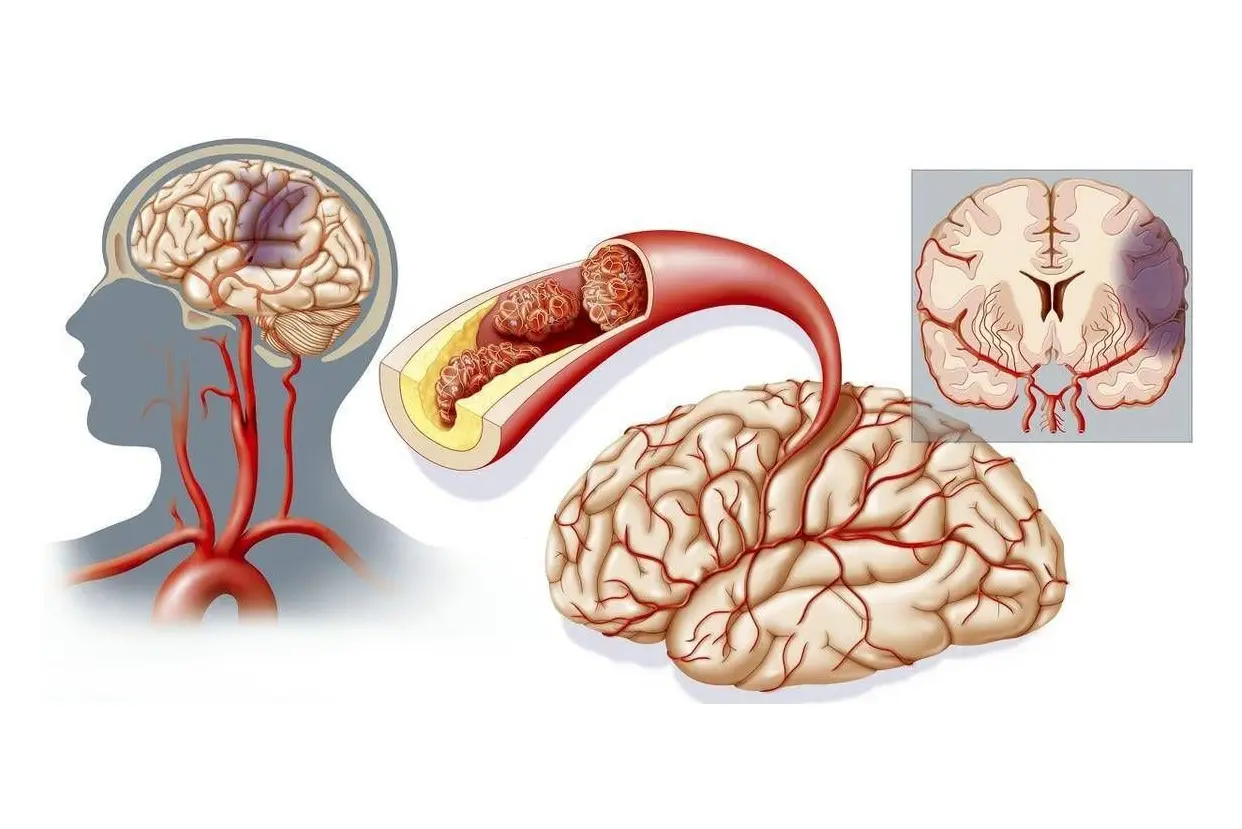

Conditions We Treat:cerebral palsy, autism, cerebellar atrophy, epilepsy, intractable epilepsy, cerebral hemorrhage, Parkinson's, Alzheimer's, sequelae of cerebral infarction, and various neurological disorders.